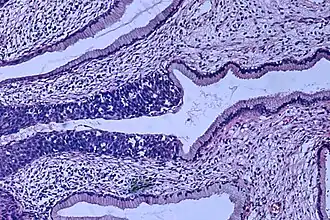

Au niveau de l’endocol, l’épithélium contient des glandes qui produisent un mucus (épithélium glandulaire). L’épithélium glandulaire est constitué d’une seule couche de cellules hautes. Il tapisse le canal endocervical et s’étend vers l’extérieur sur une portion variable de l’exocol. Au niveau de l’exocol, l’épithélium est semblable à celui de l’épiderme de la peau (épithélium malpighien). Il est constitué d’une couche profonde épaisse recouverte de plusieurs couches de cellules de plus en plus plates se superposant comme des tuiles.

La zone où se rencontre l’épithélium glandulaire et l'épithélium malpighien est la zone de jonction. 90% des cancers naissent de jonction.

La transformation cellulaire de l'épithélium malpighien par l'infection transformante débute au niveau des cellules superficielles de cette épithélium et se dirige vers la membrane basale.

Le cancer est dit invasif lorsque les cellules cancéreuses rompent la membrane basale.

Le carcinome in situ est la modification cellulaire atteignant toutes les couches cellulaires de l'épithélium malpighien sans rupture de la membrane basale,

Il existe deux types principaux de cancer du col utérin[82] :

- dans 80-90 % des cas il s'agit d'un carcinome épidermoïde qui se développe à partir du revêtement épithélial du col ;

- dans 10-20 % des cas, il s'agit d'un adénocarcinome qui se développe à partir du revêtement glandulaire du col.